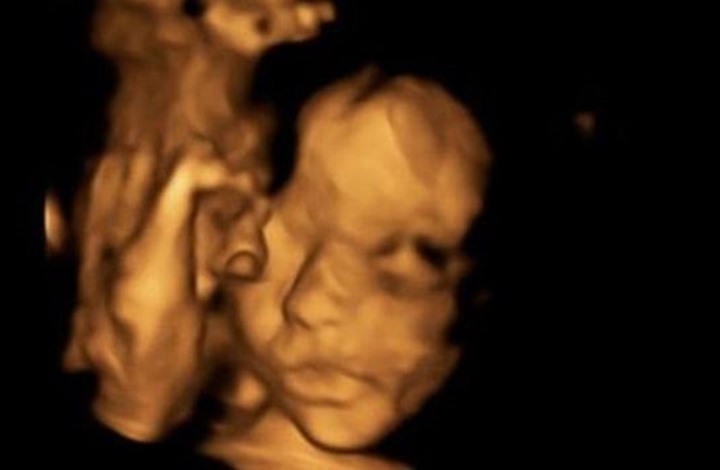

| إصلاح العمود الفقري لجنين في رحم أمه |

أجرى أطباء بريطانيون عملية باستخدم فتحة جراحية صغيرة لإصلاح العمود الفقري لجنين في رحم أمه مصاب بفتق في العمود الفقري، تعد العملية هي الأولى من نوعها في بريطانيا.وأجرى... |